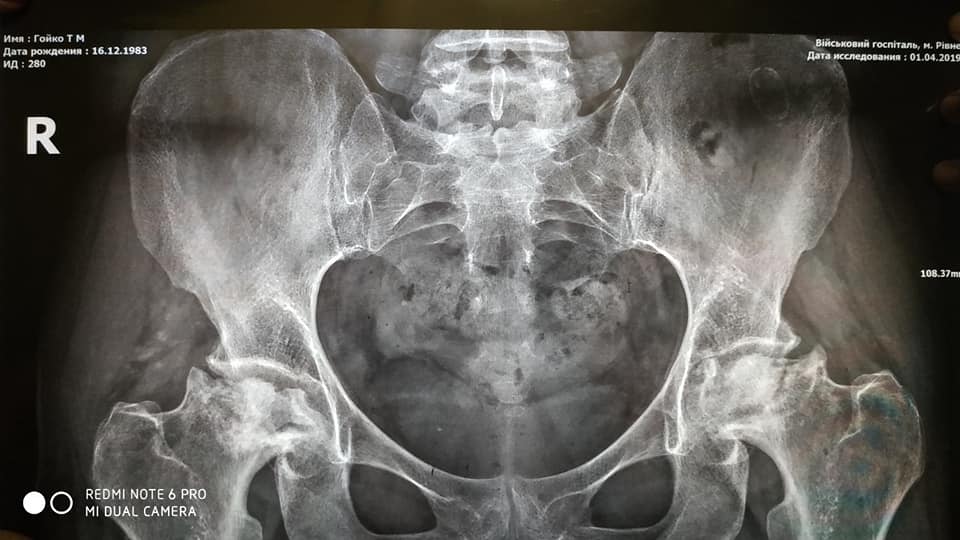

Ще у 2016 році її почав турбувати біль у паху та нозі. Лікарі сказали, що вона защемила сідничний нерв. Лікування не дало результату. Наступні 2 роки лікували спину, доки не зрозуміли, що проблема в суглобах (коксартроз 4-5 ступеня). Через півроку захворів чоловік. Діагноз: асептичний некроз кульшових суглобів (коли через порушене кровопостачання пошкоджується кісткова тканина). Операцію спочатку зробили йому, адже повинен був працювати.

Лікарі не знають, чому проявилася хвороба, думали – статеві інфекції. Також мали припущення, що в квартирі є радіація або ртуть. Радіації не знайшли, а перевірити на ртуть у Рівному немає чим. Лікарі припускають, що в Тетяни хворобу міг викликати саркоїдоз легень, який виявили в 2008 році. Та чому захворів чоловік, і досі залишається загадкою.

Лікарі запевняють: оперувати треба терміново, оскільки руйнуються кістки. Кажуть, згодом не буде куди ставити протези.